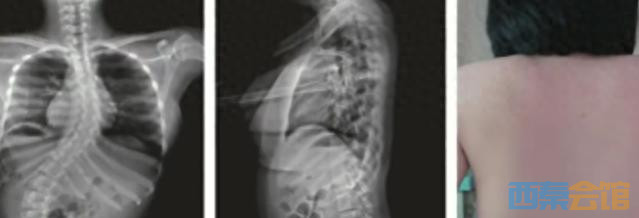

“瘫痪之后,孩子只能依靠轮椅生活,久而久之,脊柱也会出现弯曲。”朱泽章表示,不仅双手生活能力受限,心肺等多个脏器功能也因脊柱变形受到压迫。无奈之下,父母将她送到南京某医院脊柱外科就诊,进行微创矫形治疗。